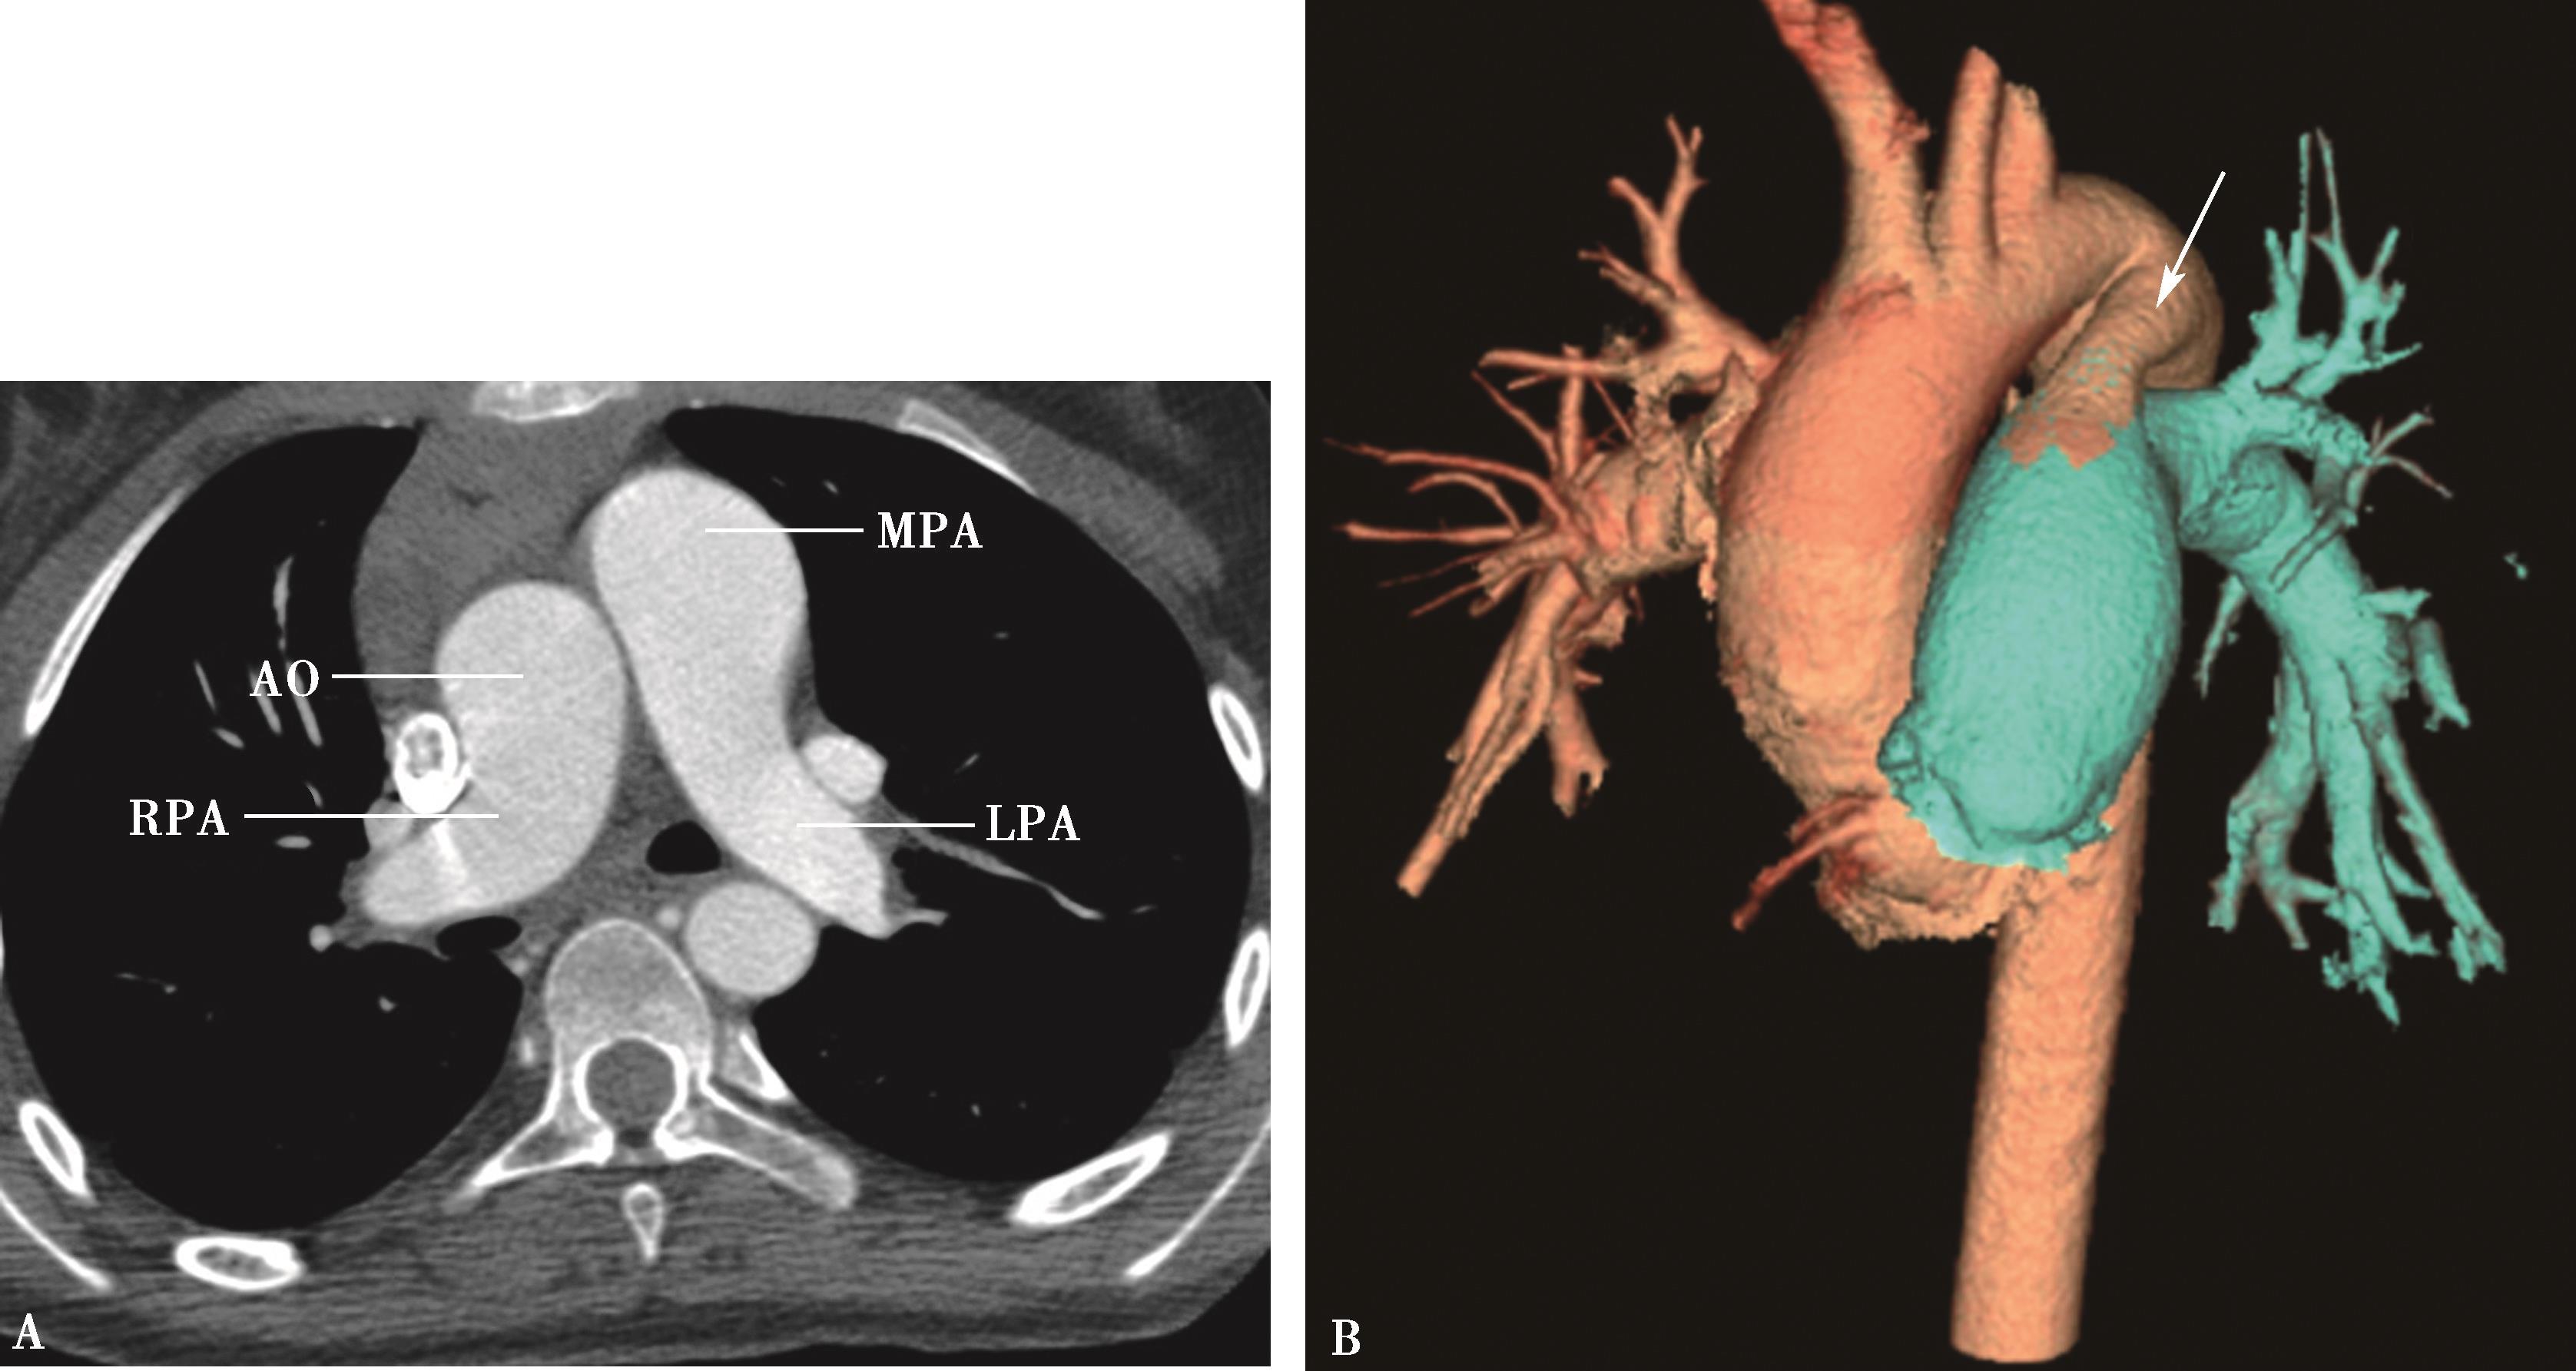

图8-1-4 常规肺动脉CT造影横断图及重建图像

图8-1-5 CTPA两期扫描应用:患者,男,37岁,二尖瓣狭窄,肺循环高压,怀疑肺栓塞。第一期右肺下叶基底段对比剂充盈不充分(ABC↑);第二期充盈充分(DEF↑),排除肺栓塞诊断